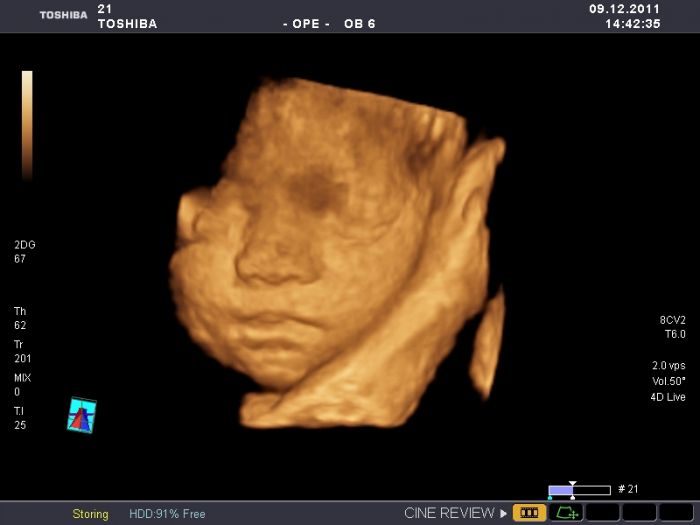

Ahoj holky,zdravím všechny takto po ránu.Skoro celou noc nespím,špatně se mi dýchá a tak jsem tu.. Do té nové diskuze miminka březen se nemůžu dostat i přesto,že jsem tu od samého začátku a jsem už i zaregistrovaná. neumíte mi s tím některá poradit čím to je? jinak čekáme holčičku a rodit budu někdy v půlce února.mám plánovaný císař,tak půjdu o něco dříve. už se nemuzu dockat,nejak uz to fyzicky ani psychicky nezvladam. pokusím se připojit foto mé maličké ve 27.tt ze 4D.Mějte se krásně.Káča

Kačí sice ti neporadím, ale musím ti pochválit malou

užasný fotečky. My bohužel na 4D nebyly tak ani nevíme jak mimčo bude vypadat.

Kačko, to je fakt nádherná fotečka...:) takhle by to mělo vypadat, ale myslim, že skoro nikomu se takovýhle fotečky nepoštěstí...:) jinak co se týče té diskuze, to budeš muset probrat s danielou a nebo rovnou s mitti...občas se asi objeví nějaké problémy...:( tak snad se to brzo vyřeší...:)